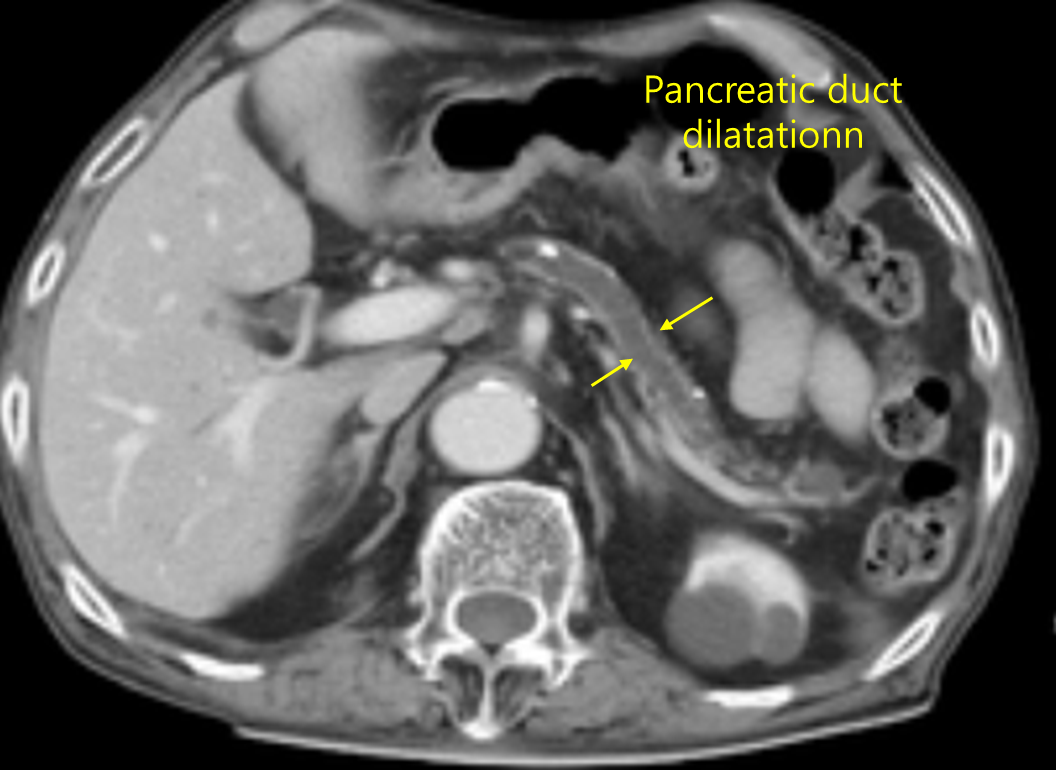

46세 여자가 7개월 전부터 간헐적인 복통과 기름이 뜨는 설사를 한다며 병원에 왔다. 10년간 거의 매일 소주 1병씩 마셨고 10갑·년의 흡연자이다. 당뇨병으로 치료 중이고 급성 췌장염을 앓은 적이 있다. 혈압 140/90mmHg, 맥박 66회/분, 호흡 20회/분, 체온 36.5℃이다. 배는 편평하고 장음은 정상이며 압통은 없다. 혈액검사 결과는 다음과 같다. 복부 컴퓨터단층촬영 사진이다. 치료는?

Img | CT: 췌장 calcification, 췌관 확장 |

• 만성적인 간헐적 복통, 지방변, 당뇨, 음주력과 흡연력, 급성 췌장염 과거력 등은 모두 만성 췌장염을 시사하는 소견이다. CT 상 calcification, 췌관 확장 소견으로부터 만성 췌장염을 진단할 수 있다.